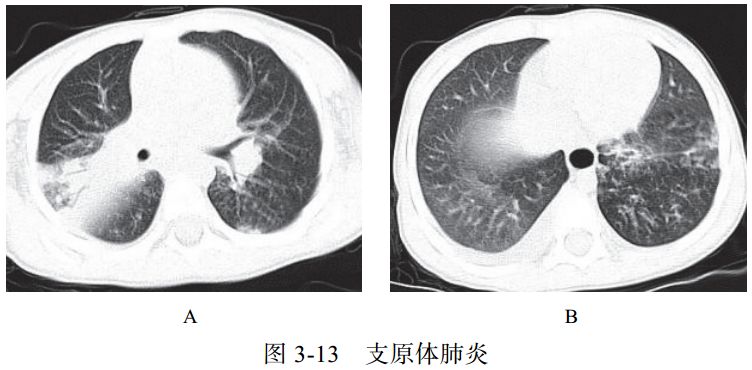

与肺部支原体感染的鉴别诊断

支原体肺炎是由支原体引起的以间质性改变为主的肺炎。支原体侵入肺内可引起支气管、细支气管黏膜及周围间质充血和水肿,多核细胞浸润,侵入肺泡可产生肺泡浆液性渗出炎症。病变范围可从小叶、肺段至大叶。多数患者症征不符:临床症状重,影像学表现较轻。

实验室检查支原体抗体呈阳性,发病 2~3 周后血冷凝集试验比值升高(可达 1∶64)。

影像学表现:

(1) HRCT 显示更清晰,呈树雾征(图 3-13A)、树芽征(图 3-13B),可出现支气管壁增厚。

(2)渗出实变较淡,常合并支气管肺炎。